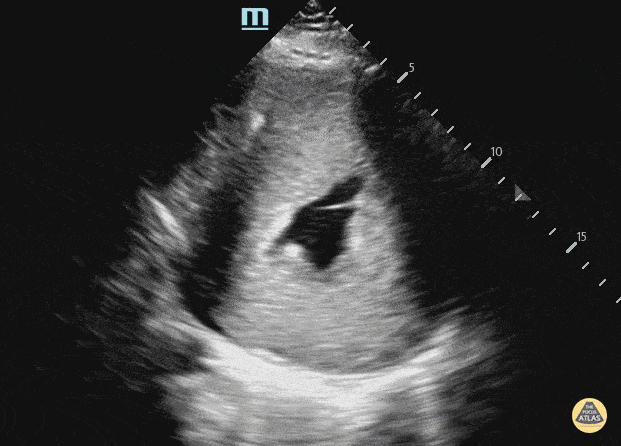

17 year old male with history of Danon disease resulting in hypertrophic cardiomyopathy. Contributor: Julia Brant, MD, Children's Colorado, @pedipocus